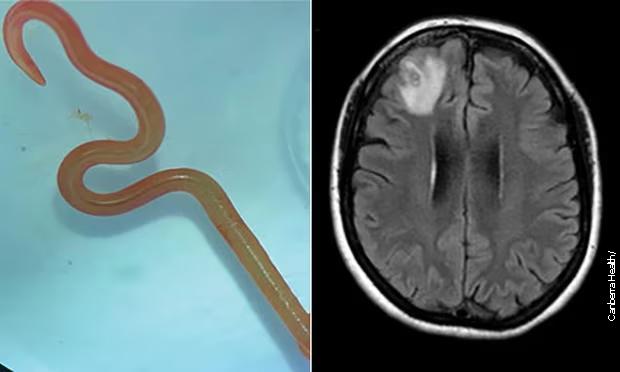

„Živ i migolji se“ – hirurzi iz mozga žene izvadili živog...